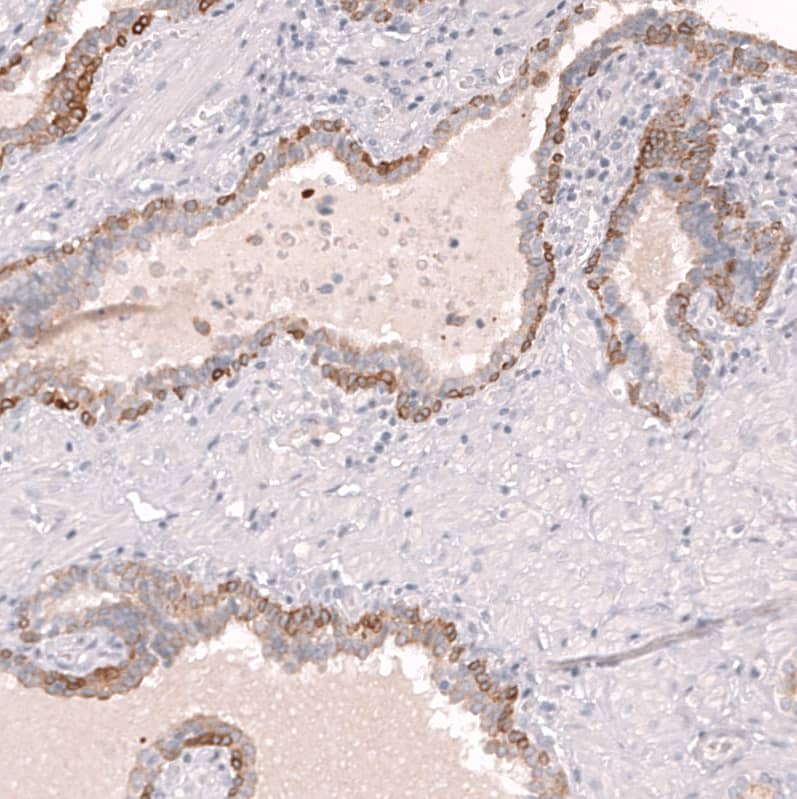

Staining of human epididymis shows strong membranous positivity in glandular cells.